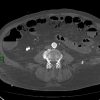

Nhồi máu ruột

» Thông tin: Nam giới – 85 tuổi.

» Lâm sàng: Đau bụng cấp.

# Dày thành ruột – Khí thành ruột – Khí tĩnh mạch mạc treo.